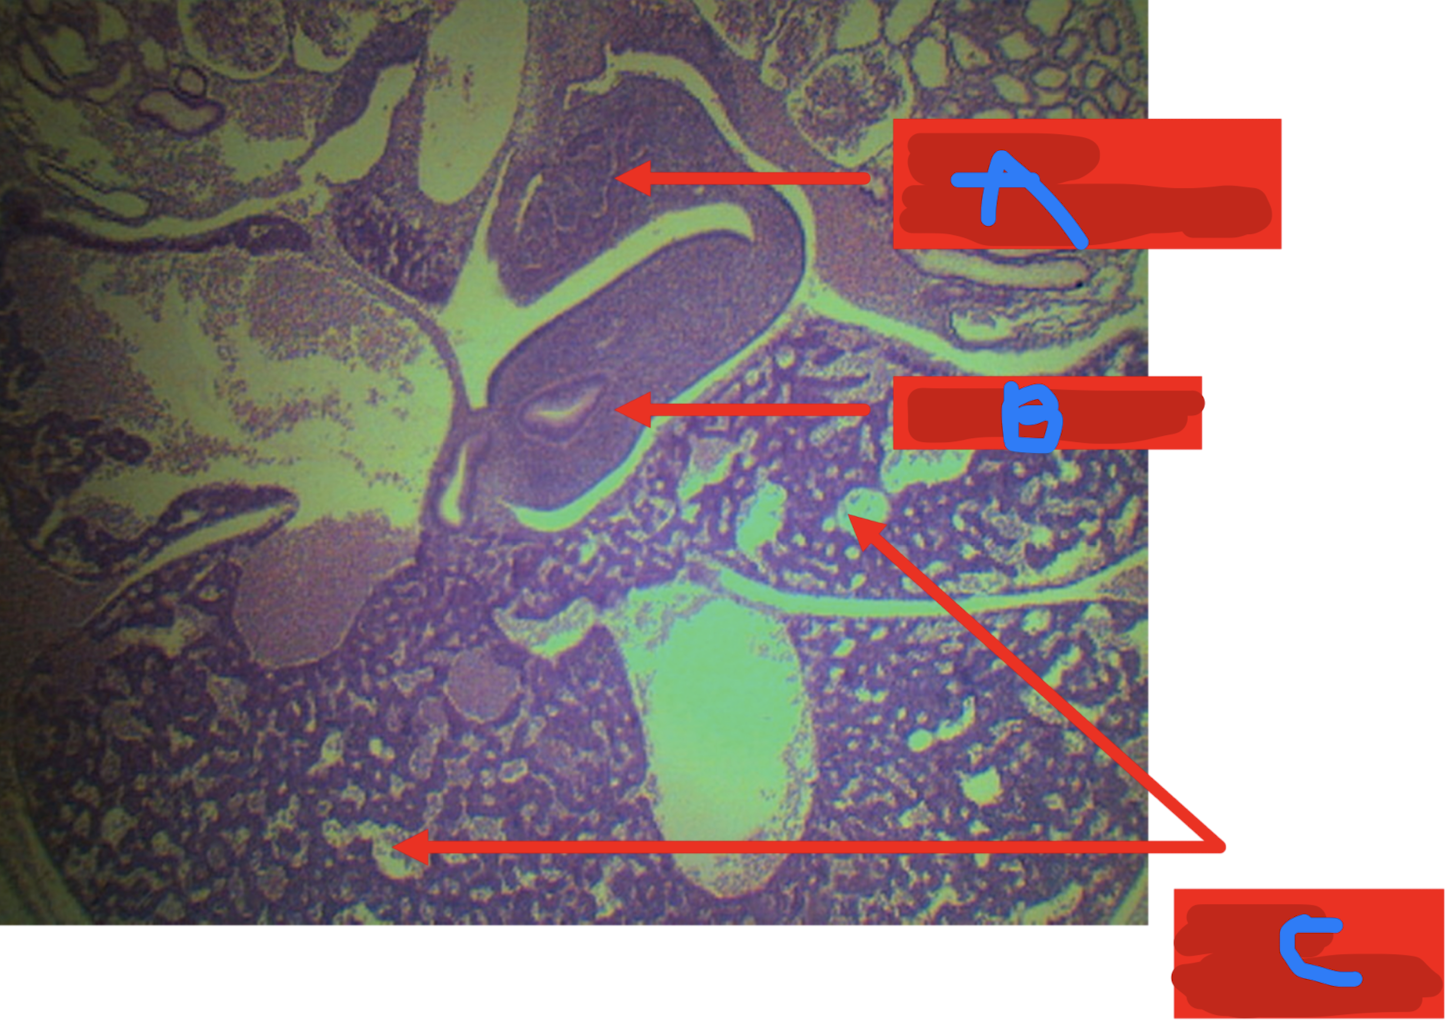

Identify the structure

A: dorsal pancreatic bud

B: ventral pancreatic bud

C: duodenum

D: liver